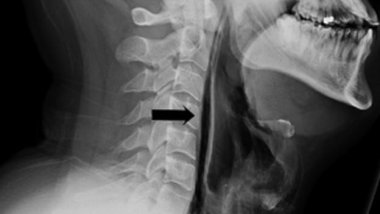

Taguri: England UK lorry with dead bodies: Vietnamese family fears daughter may be among victims Poland, Australia, Japan could join England's World Cup boycott if Russia was behind attempted murder of... Man from Leicester accidentally ruptured his throat while trying to hold back a sneeze Fire in Hampstead took life of a woman and left 20 others seeking refuge Moldova surprises Europe. 20 students completed IOE&IT qualification in 5, instead of 18 standard months Quarter of England’s rivers at risk of running dry, finds WWF Prince Harry 'in total chaos' over mother Diana's death Drones flying into prisons to be examined by new police team Sex education to become compulsory in England Recycling rates in England drop for first time England may be in deforestation state due to lack of tree planting 89-year-old veteran posts ad looking for a job to save him from boredom Storm Angus: floods hit south-west England – with more rain to come Man dead and two injured after Halloween night stabbings in England England's oldest hotel has collapsed after huge fire Moldovan team of beach football will play against Portugal in preliminaries UEFA threatens to BAR England from Euro 2016 if violence continues Euro 2016: Dozens injured as crowds of rival fans brawl 1 ABCDEFGHIJKLMNOPQRSTUVWXYZ IMPORTANTE ALTELE